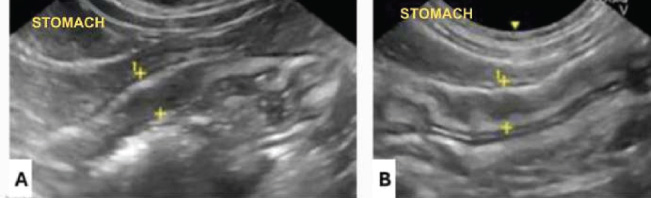

The stomach is ultrasounded caudally to the liver, close to the xiphoid process, slightly to the right (Larson and Biller, 2009). The stomach is identified by its size, regular peristalsis (four to five contractions per minute), and folds in the wall that, when empty, create a characteristic “wagon wheel” appearance (Penninck et al., 1990). The gastric wall has five distinct layers: mucosa, submucosa, muscularis, serosa, and luminal surface (König and Liebich, 2021). The mucosa and muscularis are hypoechogenic, whereas the other layers are hyperechogenic (Fig. 1) (Penninck et al., 1990; Burk and Ackerman, 1996). To measure gastric thickness, it is important to avoid folds in the stomach, which can cause a false impression of enlargement due to contractions or image artifacts, and the measurement is no more than 0.29 cm (Fig. 2) (Irom et al., 2014; Griffin, 2019). Assessment includes the analysis of thickness, stratification of layers, peristaltic activity, intraluminal content, and perigastric structures, such as lymph nodes, omentum, and the presence of gas or free fluid (Larson and Biller, 2009).

Fig. 1. Ultrasound (linear transducer, 8 MHz) of the stomach of an adult cat in a cross-section. Stomach (S) with the appearance of a wagon wheel, liver (L) cranial to the stomach, and abdominal wall (AW) ventral to the stomach. Source: Personal archive, 2025.

Fig. 2. Ultrasound (linear transducer, 8 MHz) of the body of the stomach of a cat in the longitudinal section. Gastric wall (between cursors) with a thickness of 0.29 cm, preservation of stratification, slightly rough aspect. Source: Personal archive, 2025.

Fig. 4. Gastric ultrasonography in a longitudinal section of a feline (microconvex transducer, 8 MHz). (A) Gastric wall thickness between the cursors measuring 0.62 cm and (B) 0.53 cm. Both thickened. Source: Personal archive, 2025.